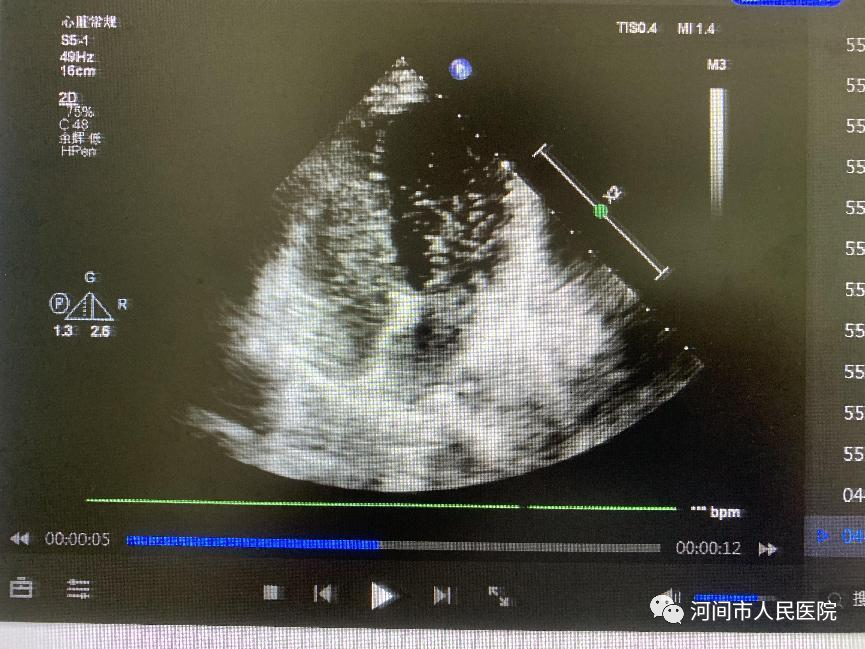

异常时心脏超声左心内出现微泡,TCD检测大脑中动脉发现微栓子信号。